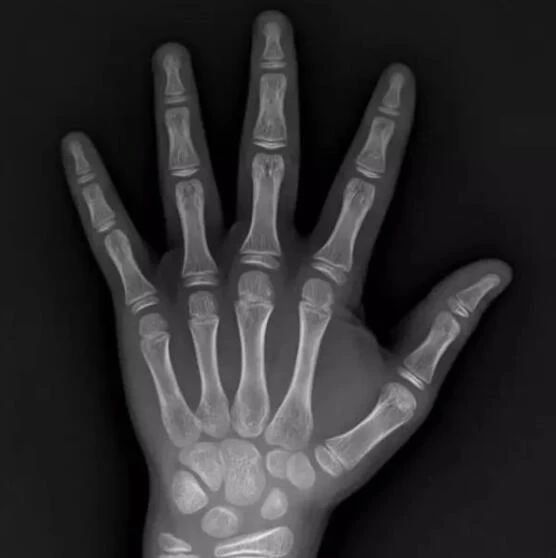

一、什么是骨龄:

骨龄是人体骨骼发育成熟程度,通过左右腕骨X线摄片后进行骨龄测评,可及时了解儿童的生长发育潜力以及性早熟的趋势,并可预测儿童成年身高,了解剩余生长空间。